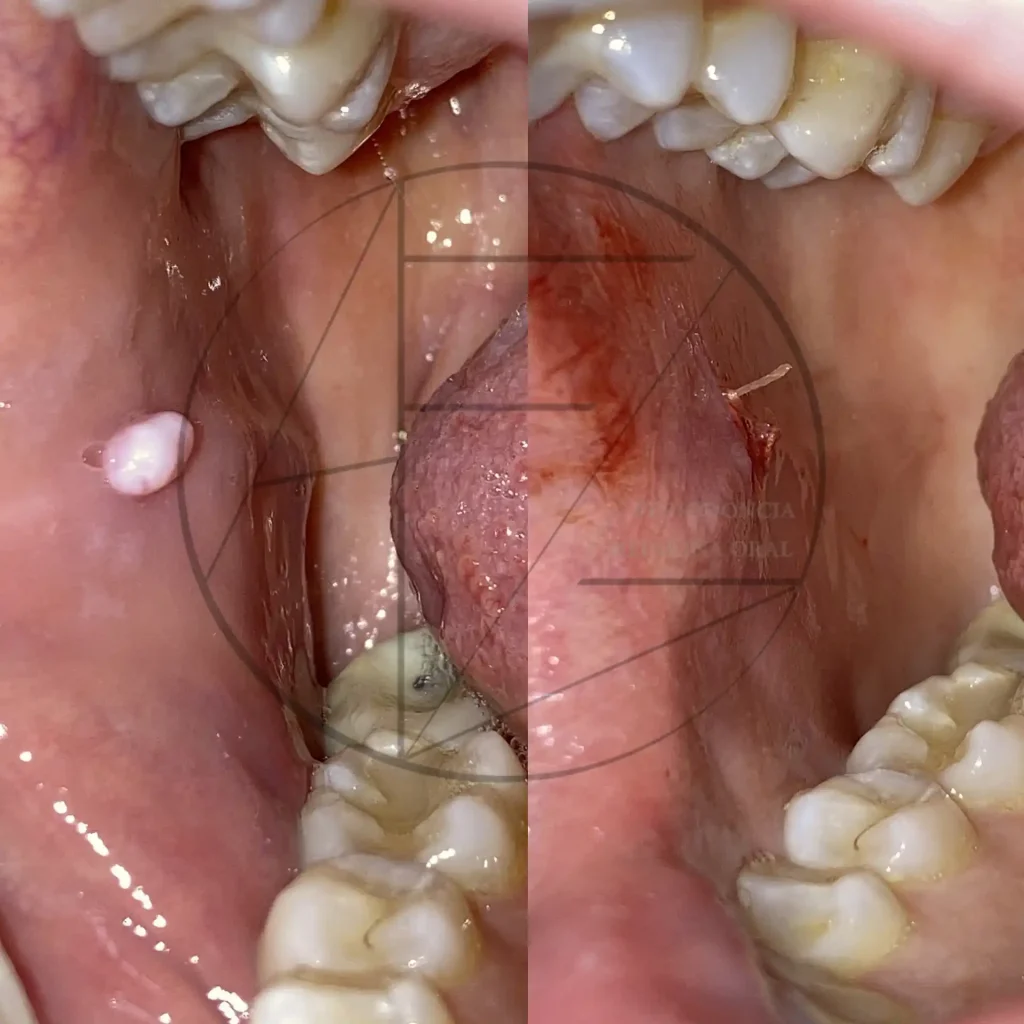

Papiloma